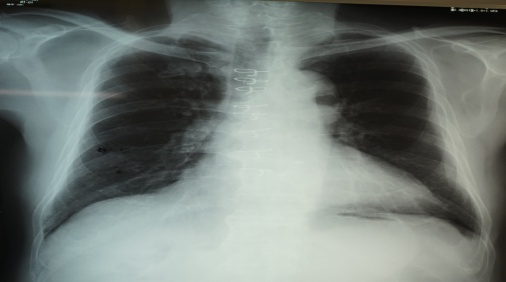

1. 初回~最新回XPとCT共に胸膜プラーク有9名(39.1%)平均年齢65.1(62~72)歳【写真1】

【写真1】胸膜プラークの胸部X線写真 典型的な経過5)

胸部X線写真で胸膜プラークのある場合、胸膜プラークは経年的に厚く大きくなり徐々に石灰化した【写真1】。胸膜プラークはCTで66~80歳で初めて認められ、70台,80才の胸部CT写真撮影の必要性が認められた【写真3】。高濃度石綿ばく露をうけた23名中4名に80台でも胸部CTで胸膜プラークのない群が確認された。肺がんによる死亡が3名に認められ、胸膜プラーク有は1名で2名はXP・CT共に最後までプラークなしだった。職業性石綿ばく露を受けた集団は、退職から永眠までの期間の健診体制を必要とし、胸部X線CT写真を併用し観察する意義が再確認された5)